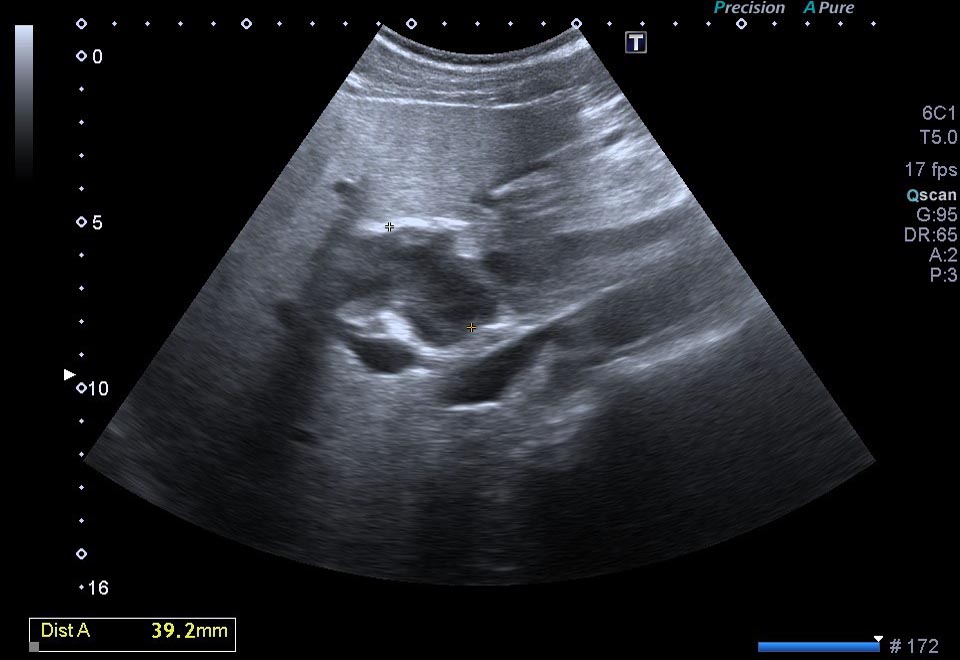

1. ¿Cuál de los siguientes hallazgos NO se encuentra en las imágenes ecográficas?

- A. Lesión hipoecoica que engloba la arteria hepática.

- B. Lesión hipoecoica que contacta con la cabeza pancreática.

- C. Dilatación del colédoco y del Wirsung.

- D. Permeabilidad de arteria hepática.

- E. Permeabilidad de la porta.